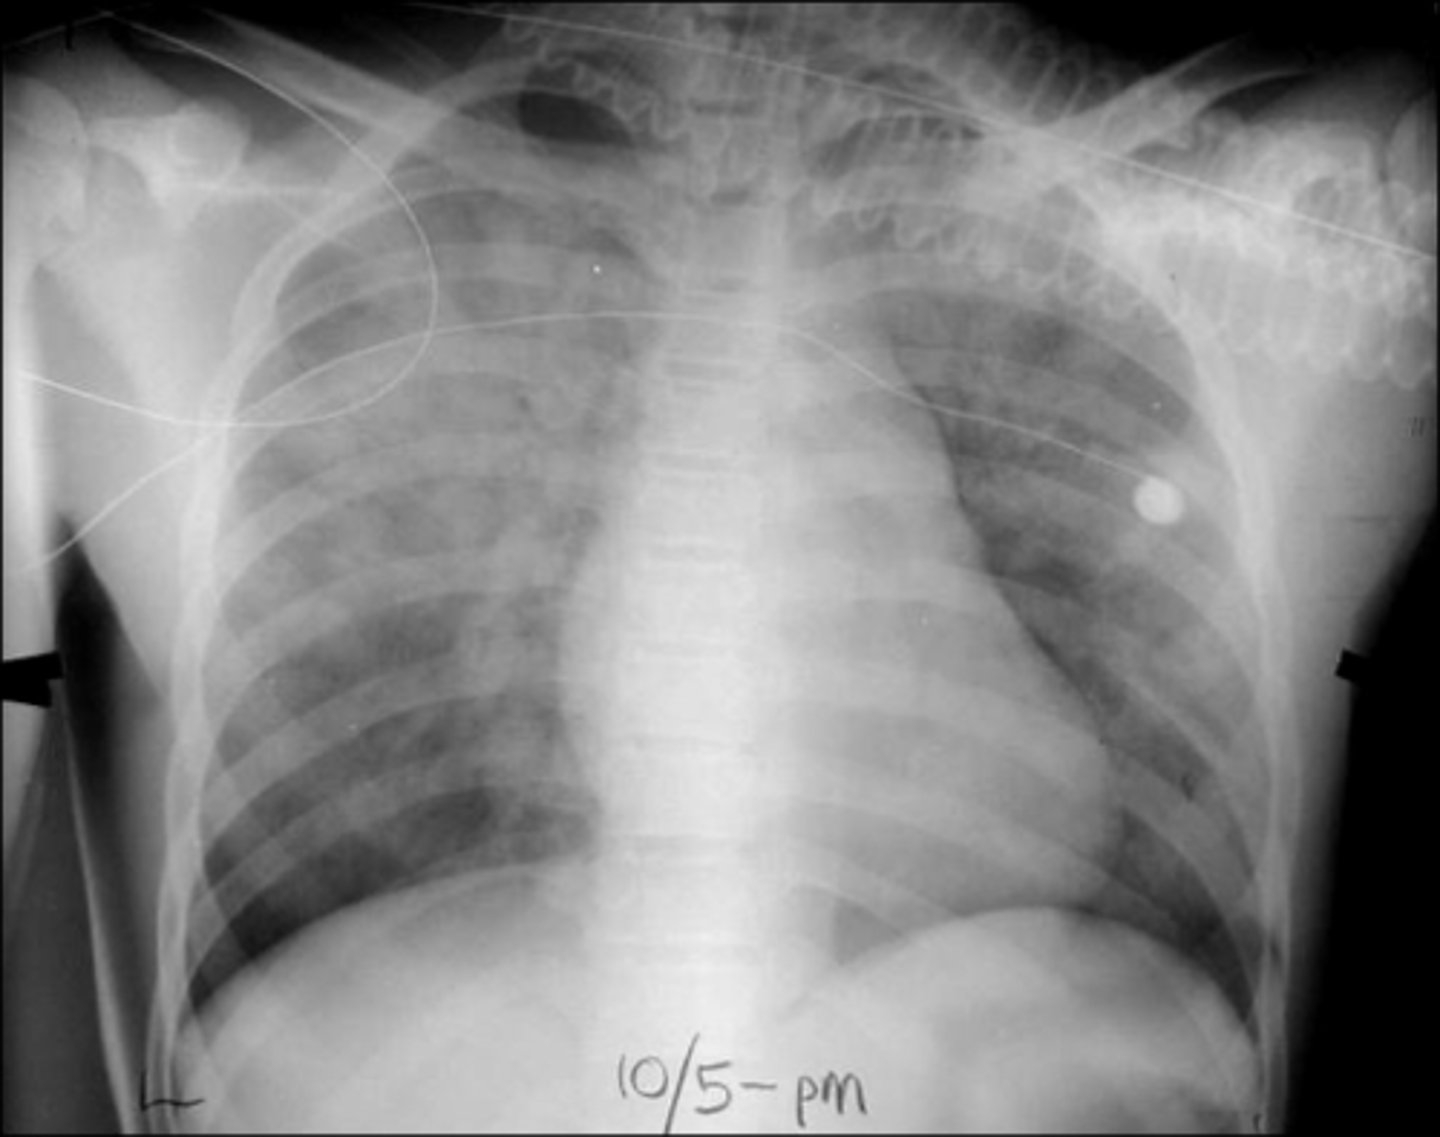

ARDS

ARDS

Bilateral interstitial infiltrates

Bilateral pleural effusion